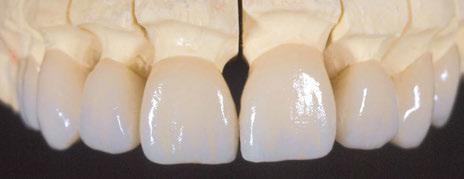

Flujo de trabajo preciso para la reproducción cerámica sin renunciar a nada, por Luis Miguel Vera. 64

uando se trata de diseñar una prótesis de arcada completa sobre implantes y con carga inmediata es necesario transmitir al laboratorio dental toda la información para poder realizar un diseño correcto de la prótesis provisional inmediata. Se trata de obtener el mejor resultado desde el punto de vista estético y funcional con esa primera prótesis provisional fija. Por eso se ha creado la técnica Di2gitalArch®, en la que el elemento i2 servirá como estructura de referencia fija que facilite la alineación y superposición de los archivos virtuales obtenidos, mediante escáner intraoral, en diferentes situaciones clínicas de un mismo paciente.

Diseñado fundamentalmente para procedimientos de carga inmediata con un escáner intraoral, y con la finalidad de copiar o recrear la situación previa o inicial del mismo, el sistema permite la superposición de todos los archivos que contengan el elemento i2 en la misma posición espacial y obtener un

flujo de trabajo nuevo, tanto a nivel clínico como en el proceso de diseño CAD/CAM, más rápido, fácil y preciso, tanto a nivel funcional como estético.

Sistema 1.0 y Sistema 2.0. La principal diferencia entre ambos es que el Sistema 1.0 es un sistema ideado para situaciones no quirúrgicas (Figuras 1-44).

SISTEMA 1.0

Está compuesto por un tornillo autorroscante de fijación de 2 mm de diámetro y de 10,5 o 12,5 mm de longitud, que se usa para fijar el scanbody Di 2 gitalArch® al maxilar del paciente y un scanbody diseñado específicamente para esta aplicación, en cuanto a sus dimensiones y morfología. Otros diseños de scanbody no han resultado plenamente efectivos ya que se trata de alinear todo un maxilar.